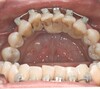

Cas 7c

L’attelle métallique mandibulaire réalisée il y a 20 ans est toujours satisfaisante.

Cas 7d

Vue palatine de la nouvelle attelle en résine maxillaire.